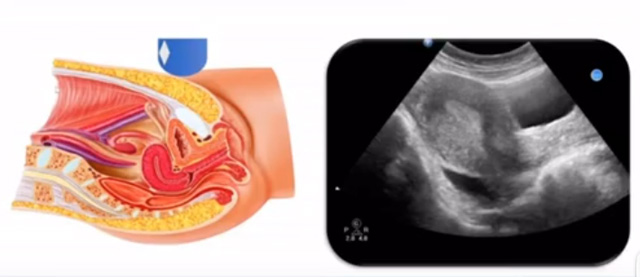

女性生殖系統包括內、外生殖器官及其相關組織以及鄰近器官,其中內生殖器是我們超聲檢查的主要對象。那么內生殖器包括陰道、子宮還有輸卵管及卵巢。輸卵管及卵巢稱為子宮附件。子宮是倒置梨形,但是它是空腔厚壁肌性器官。它的正常值在育齡婦女。超聲探頭放在貼近腹壁盆腔上面位置,來看這個子宮在超聲上面的表現。從輪廓上來講,和示意圖是一樣的。這就是在超聲上面顯示的一個子宮的圖片。子宮在不同的時期與子宮頸的比例。成年婦女指的是育齡婦女為2:1子宮體是比較大的,嬰兒期為1:2說明宮頸比較大,絕經期1:1。所以我們在看到子宮圖時候可以根據宮體宮頸比例大致可以推測屬于哪個時期的婦女。另外還可以根據比例大小來推斷是一個正常子宮還是異常子宮。

子宮從外到內,漿膜層、肌層、粘膜層。宮體部宮頸為梭形結構。宮腔為上寬下窄的三角形,連接為峽部。子宮有什么功能呢?月經血產生跟排出通道,精子運行通道受精作用。囊胚著床及胎兒發育、生長的場所。分娩時產生宮縮使胎兒、胎盤娩出。未孕的子宮是很小的,已孕子宮就非常大,平均胎兒都有6斤重。所以這個后壁就體現出來。輸卵管由子宮角部向外延伸,為一對細長而彎曲的管道,呈管狀中空結構,大概長度是8-14厘米,粗1-4毫米,它的下方為卵巢和闊韌帶。間質部是厚一點的,峽部是比較窄的地方,壺腹部,漏斗部。正常情況下,輸卵管在普通超聲DR難以顯示。